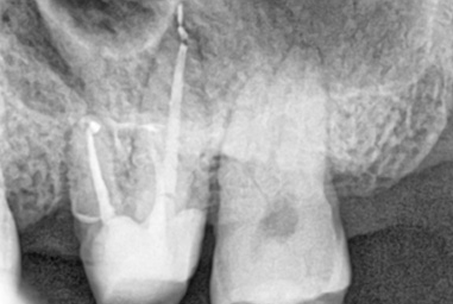

외과적 신경치료라 불리는 치근단 절제술은

재신경치료가 불가능한 경우에 행해지는 전문적인 시술입니다.

잇몸을 열고 염증의 원인이 되는 치아뿌리를 3MM 잘라낸 후

MTA라는 특수충전재료로

뿌리 끝부분을 충전하는 술식입니다.

치근단절제술은 치근단절제술 전용 특수기구와 MTA라는

특수재료를 사용해야만

제대로 된 치료가 이뤄질 수 있습니다.